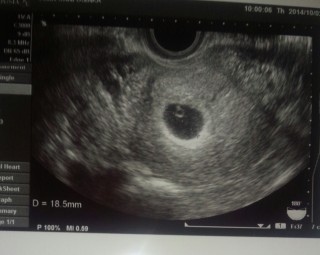

心拍確認出来たのが嬉しくて、胎嚢や胎芽のサイズを聞き忘れてしまいました。未だに後悔…σ^_^;

前回流産しているので不安だったけど胎芽みえて心拍確認出来ました(^∇^)次は2週間後!